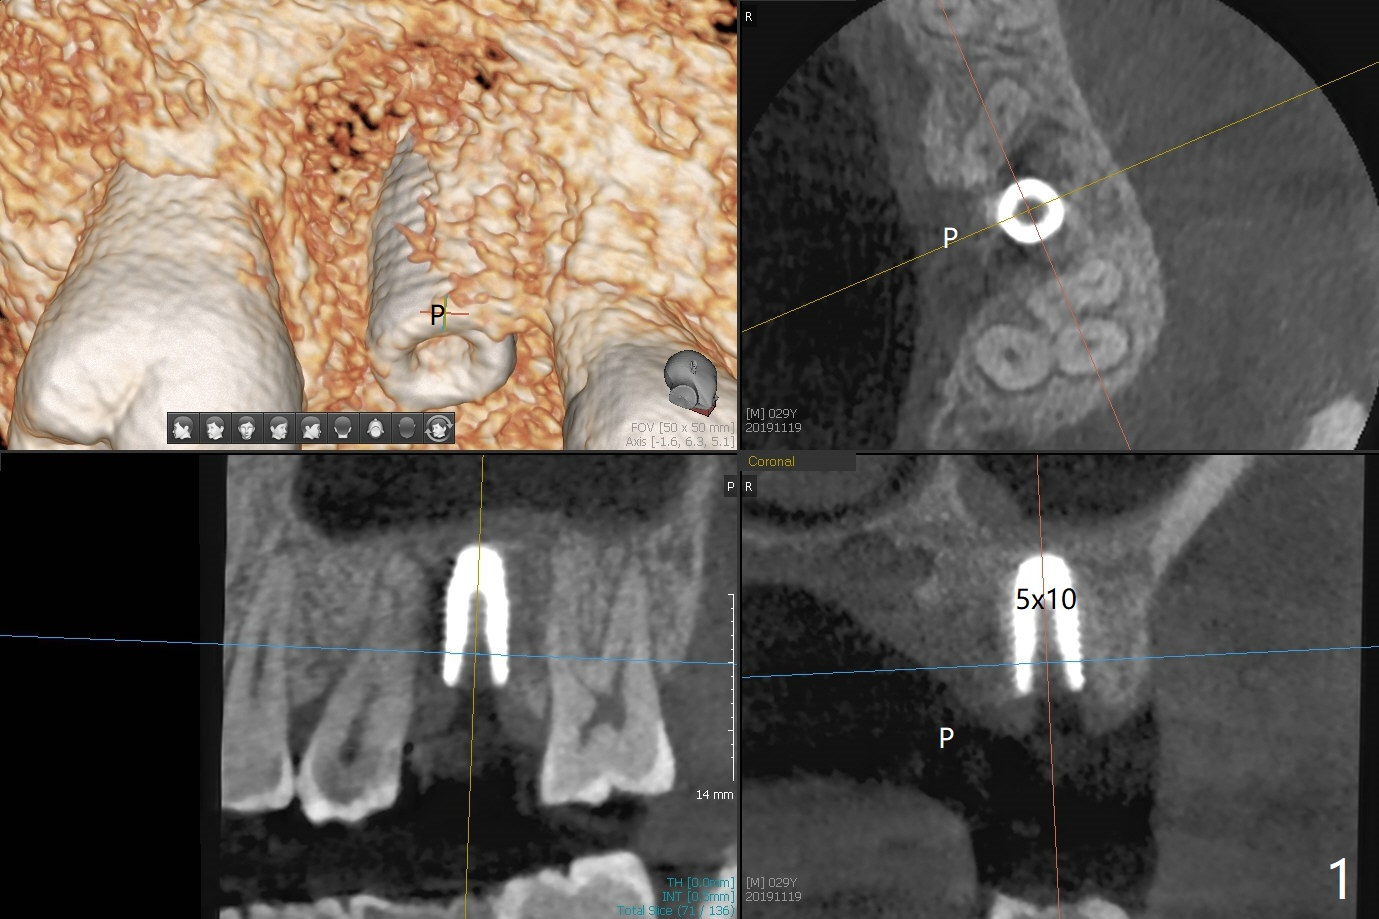

Low bone density is confirmed during osteotomy at #14 (6 months post socket preservation).  Underprep is adopted: after use of 3.5x10 mm drill instead of 4.5x10 mm one, a 4x10 and 4.5x10 mm dummy implant are placed for bone condensation.  When a 5x10 mm definitive implant is placed, it is unable to be placed to the depth.  After use of 4.0x10 mm, the final implant reaches depth ~ 1 mm more than planned.  But there appears no bone palatal to the implant clinically.  Small-field CT is taken.  In fact there is crestal bone palatal to the implant, but in small amount and in low bone density (Fig.1,2).  The implant should have been designed to be placed more buccal (Fig.3 arrow).  The implant also looks to be placed too close the root of the tooth #13, probably related to the rotation of #13 (Fig.4).  Unfortunately the patient does not agree to have limited orthodontics.  After palatal bone graft, GEM Cap is used to close the access with periodontal glue (Fig.5).  Spacer/periodontal dressing should have been used.  The wound heals 8 months postop, but 2-3 palatal threads are exposed with uncover.  After 6 mm profile drill and placement of a 6x4 mm healing abutment, allograft is placed palatal (Fig.6).  Upper Molar Immediate Implant, Trajectory II Shield Next Case of Buccal Defect  SP Xin Wei, DDS, PhD, MS 1st edition 11/19/2019, last revision 09/19/2020